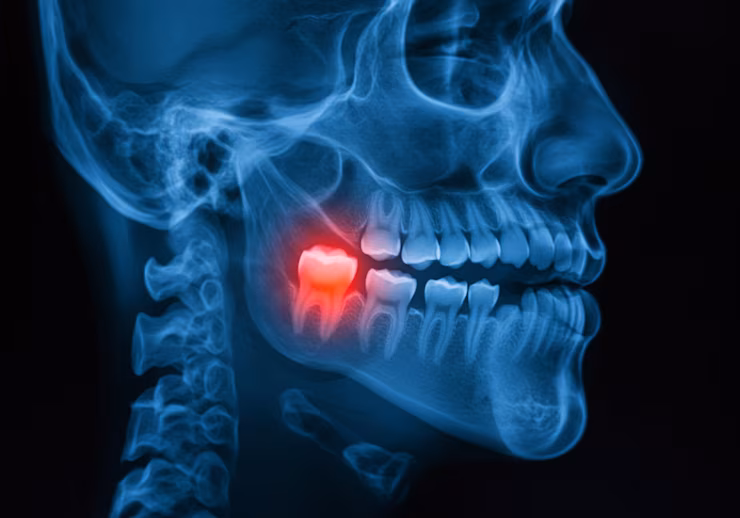

Uno de los motivos más frecuentes de consulta en urgencia dental en Concepción es la muela del juicio. Ya sea por dolor, infección o falta de espacio en la arcada, realizamos su extracción con técnicas modernas, anestesia local y un enfoque centrado en tu bienestar.

Un diente quebrado puede causar molestias, sensibilidad e incluso infecciones si no se trata a tiempo. En nuestra clínica evaluamos cada caso y ofrecemos soluciones como reconstrucciones, endodoncia o extracción según corresponda, todo dentro del servicio de urgencia dental.